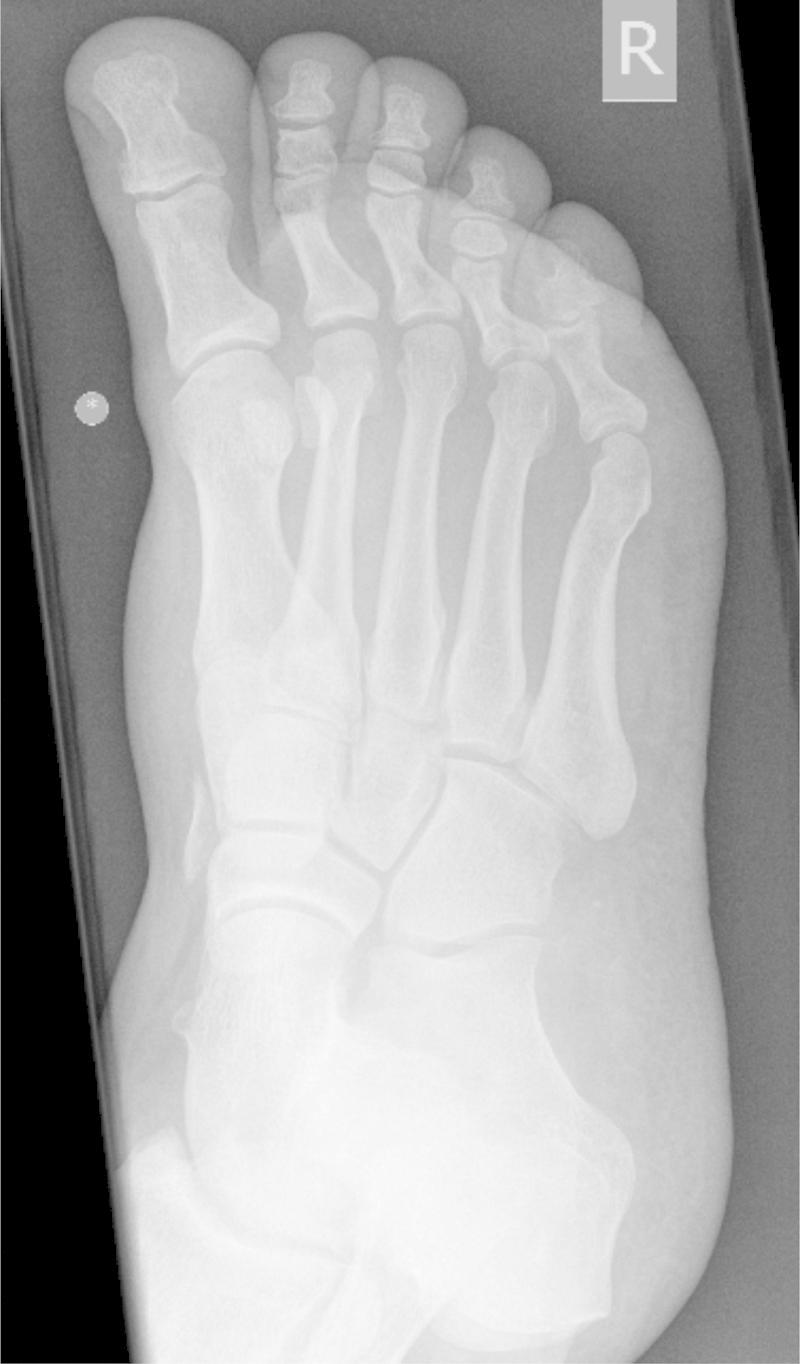

A 48 year old male sustained a crush injury to his right foot when it became stuck in a vertical industrial fan at work. He attended A & E complaining of swelling of the dorsum of foot. On examination, there was tenderness at the base of the first metatarsal. X-ray revealed an avulsion fracture of the first metatarsal, and MRI showed rupture of tibialis anterior. The patient underwent surgical repair 10 days later, with post-operative management in a non-weight bearing, then weight bearing cast. X-ray at 8 weeks showed that the fracture had healed. The patient had a course of physiotherapy and was followed up at 6 months to assess pain and function.

一名48岁男性在工作时右脚卡在垂直的工业风扇中,导致右脚挤压伤。他前往急诊室就诊,主诉足背肿胀。检查时,第一跖骨基部有压痛。X线显示第一跖骨撕脱骨折,磁共振成像(MRI)显示胫前肌腱断裂。患者10天后接受了手术修复,术后采用非负重,然后是负重石膏固定。8周时的X线显示骨折已愈合。患者接受了一个疗程的物理治疗,并在6个月时进行随访以评估疼痛和功能。